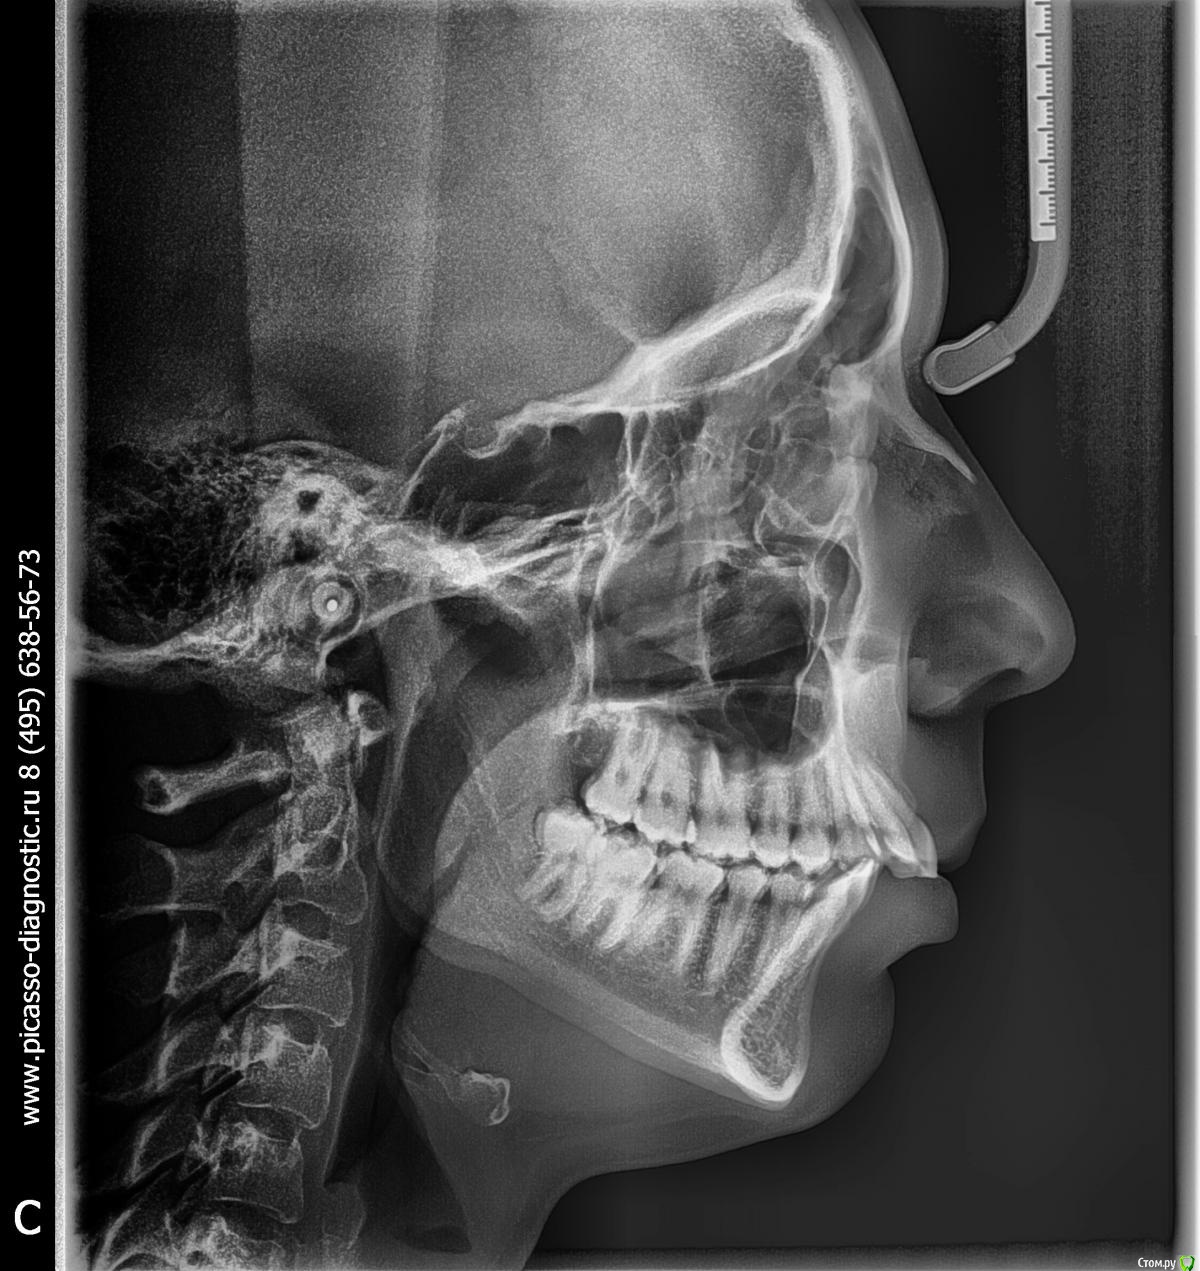

Elena_Mnzh Опубликовано 19 ноября, 2016 Поделиться Опубликовано 19 ноября, 2016 (изменено) 23 года, дистальный прикус,зубы ровные, визуально всё нормально,но челюсть неприятно выпирает. план лечения: удаление н.8ок и верхних 4ок, установка брекетов. Подскажите, пожалуйста, необходимо ли удаления? Я сама понимаю и вижу, что вроде да, но окружение запугивает байками про расхождение зубов или западющий прикус. И второй вопрос:насколько серьёзная проблема? Помогут ли брекеты или есть смысл в хирургическом лечении? И, последнее, какие негативные последствия, если я оставлю прикус в таком же состоянии?Заранее большое спасибо за ответы! Изменено 19 ноября, 2016 пользователем Elena_Mnzh Ссылка на комментарий

Yana guapa Опубликовано 23 ноября, 2016 Поделиться Опубликовано 23 ноября, 2016 23 года, дистальный прикус,зубы ровные, визуально всё нормально,но челюсть неприятно выпирает. план лечения: удаление н.8ок и верхних 4ок, установка брекетов.Подскажите, пожалуйста, необходимо ли удаления? Я сама понимаю и вижу, что вроде да, но окружение запугивает байками про расхождение зубов или западющий прикус. И второй вопрос:насколько серьёзная проблема? Помогут ли брекеты или есть смысл в хирургическом лечении? И, последнее, какие негативные последствия, если я оставлю прикус в таком же состоянии?Заранее большое спасибо за ответы!все планы лечения имеют право быть. в каждом из них есть свои плюсы и минусы. выбирать только вам.при удалении верхних четверок профиль у вас еще сильнее ухудшится (не обижайтесь, просто у вас сейчас нижняя челюсть стоит кзади, а потом еще и верхняя губа уйдет. это никак не вписывается в каноны современной красоты с пухлыми губками и тд))) )если НЕ удалять четверки, то свою верхнюю челюсть вы оставляете как есть (только наклон резцов поправить надо), а нижнюю челюсть надо будет поставить в правильное положение. Уж каким способ это будете делать решать вам и вашему врачу (перемещение с помощью брекетов и пружин или хирургия). все взвешивается, рассчитывается и принимается решение.п.с. 8-ки удаляйте, даже если лечится на брекетах не будете (уж очень они у вас высоко в отличии от других зубов прорезались, страдает сустав) Ссылка на комментарий